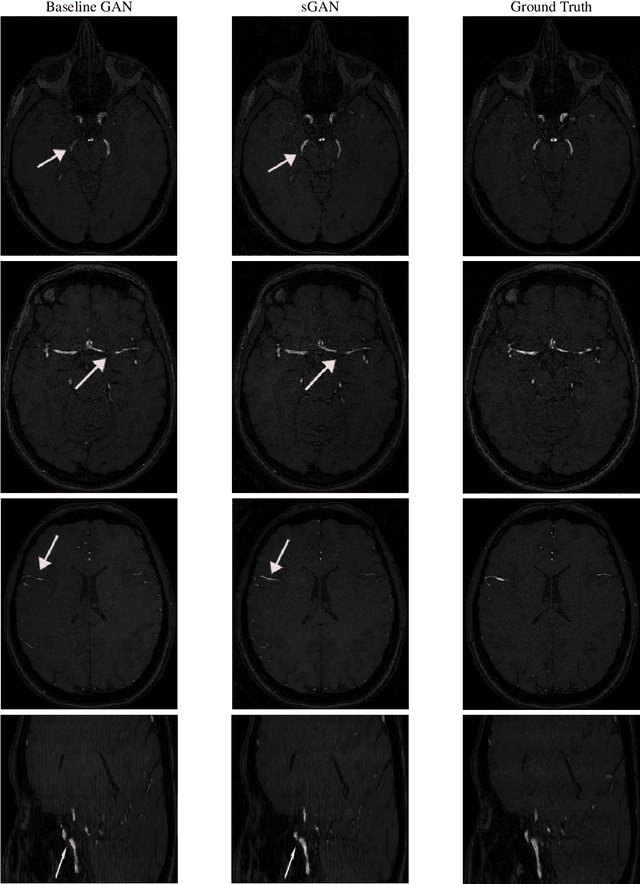

Magnetic Resonance Angiography (MRA) has become an essential MR contrast for imaging and evaluation of vascular anatomy and related diseases. MRA acquisitions are typically ordered for vascular interventions, whereas in typical scenarios, MRA sequences can be absent in the patient scans. This motivates the need for a technique that generates inexistent MRA from existing MR multi-contrast, which could be a valuable tool in retrospective subject evaluations and imaging studies. In this paper, we present a generative adversarial network (GAN) based technique to generate MRA from T1-weighted and T2-weighted MRI images, for the first time to our knowledge. To better model the representation of vessels which the MRA inherently highlights, we design a loss term dedicated to a faithful reproduction of vascularities. To that end, we incorporate steerable filter responses of the generated and reference images inside a Huber function loss term. Extending the well- established generator-discriminator architecture based on the recent PatchGAN model with the addition of steerable filter loss, the proposed steerable GAN (sGAN) method is evaluated on the large public database IXI. Experimental results show that the sGAN outperforms the baseline GAN method in terms of an overlap score with similar PSNR values, while it leads to improved visual perceptual quality.